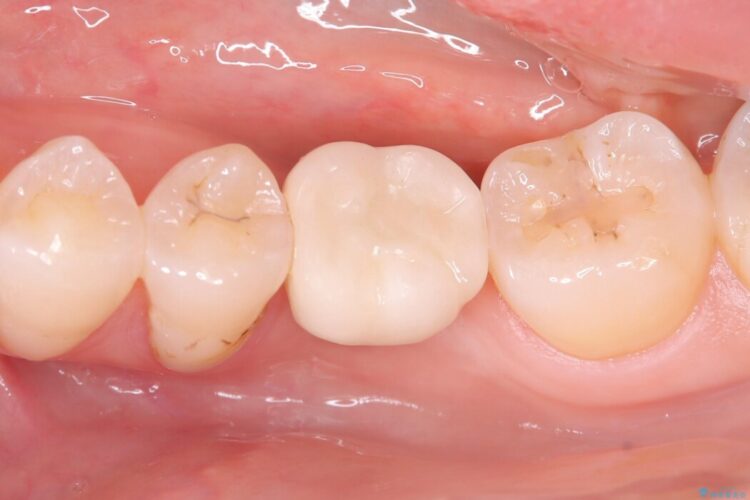

一般的に、骨が少ない場所への埋入は高度な技術を要しますが、今回は適切なサイズ(8.5mm)を選択し、埋入する深さを緻密にコントロールすることで、周囲の神経や重要な組織を傷つけることなく安全に処置を完了しました。

現在はインプラントが骨としっかり結合し、被せ物を装着して力強く噛めるようになっています。長期間の放置によって低下していた咀嚼機能が回復し、「もっと早く相談すればよかった」と喜んでいただけました。